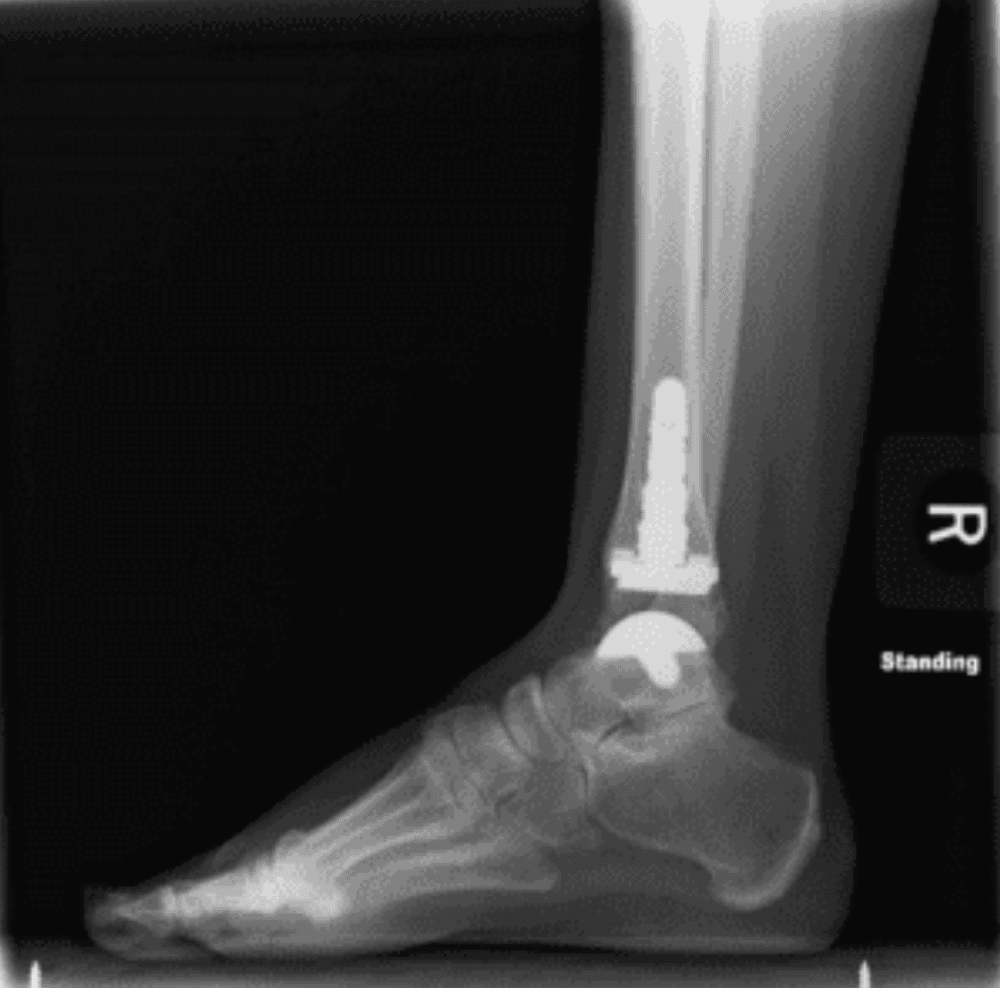

During ankle replacement surgery, an orthopedic surgeon uses an artificial implant to replace the broken ankle joint. The ankle joint forms from the shinbone resting on top of the talus, or foot bone.

The damaged pieces of your tibia and talus bones will next be removed by your surgeon. Artificial metal joints will be attached to the remaining bone surfaces, with a piece of plastic put between them, by your surgeon.

Ankle replacement surgery, commonly called ankle arthroplasty, is a significant procedure used to relieve ankle discomfort. The bottom section of the shin bone and the top of the highest bone on the foot are removed by a surgeon. Plastic or metal parts are used to replace the ankle.